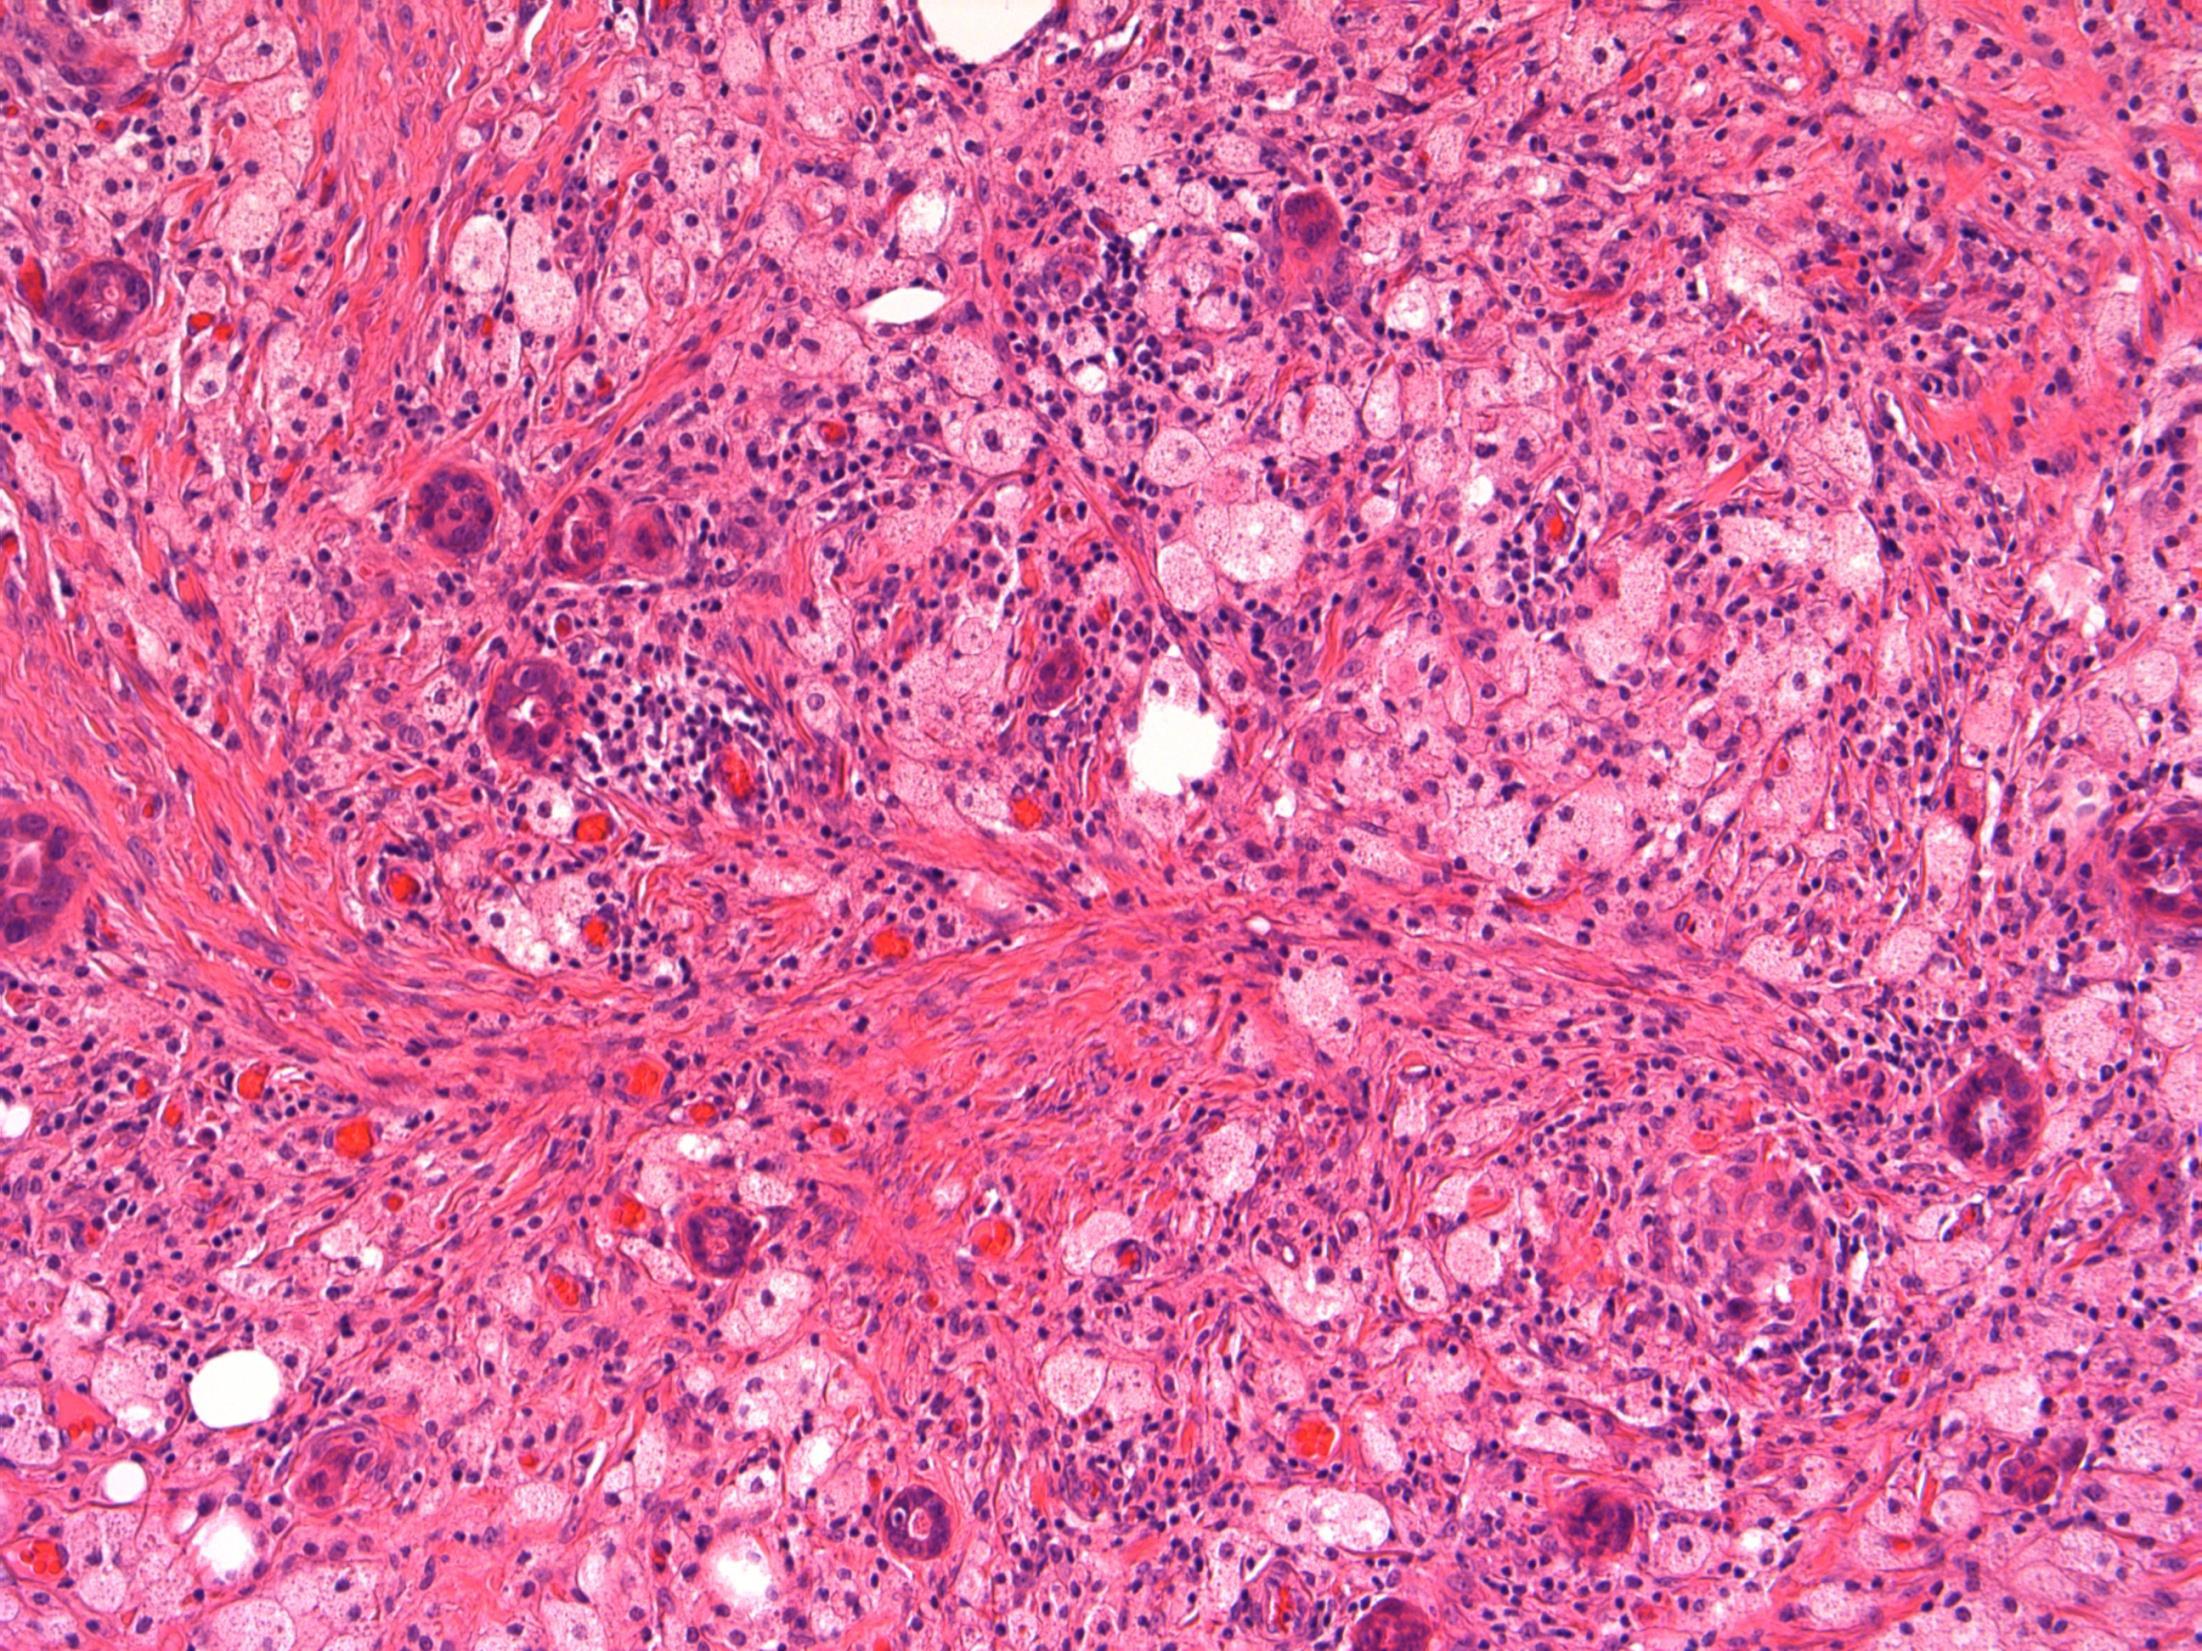

64F. Incidental imaging finding of nodule measuring 4cm in segment 2 of liver ? HCC.

Liver lobe resection received.

Case

14 •

Liver - angiomyolipoma

14

HMB45 CD117 AE1/3 SMA

Liver Description: Liver containing well circumscribed spindle cell tumour with 3 components – smooth muscle cells (predominant), adipose tissue and blood vessels. Diagnosis: angiomyolipoma Differential Diagnosis: Leiomyoma (usually no prominent vascular or adipose component, negative for HMB45) GIST (CD117+) Mets of sarcoma / spindle cell carcinoma – more atypia Plan: IHC: SMA+, HMB45+, CD117-, AE1/3+ Correlate with clinical history ? Tuberous sclerosis etc Comments: • Liver is 2nd commonest site after kidney • Often detected incidentally, usually benign • May be sporadic but is associated with tuberous

and with TSC2 / PKD1 contiguous gene

(especially if

AML

sclerosis

syndrome

bilateral/multifocal).

3.5 Clinical features, associations 3.0 Differential diagnosis and use of IHC 2.5 Description with diagnosis or DD including AML 2.0 Differential diagnosis with mention of AML but favouring other diagnosis 1.5 Differential diagnosis with no mention of AML or a benign diagnosis 1.0 Malignant diagnosis Case 14